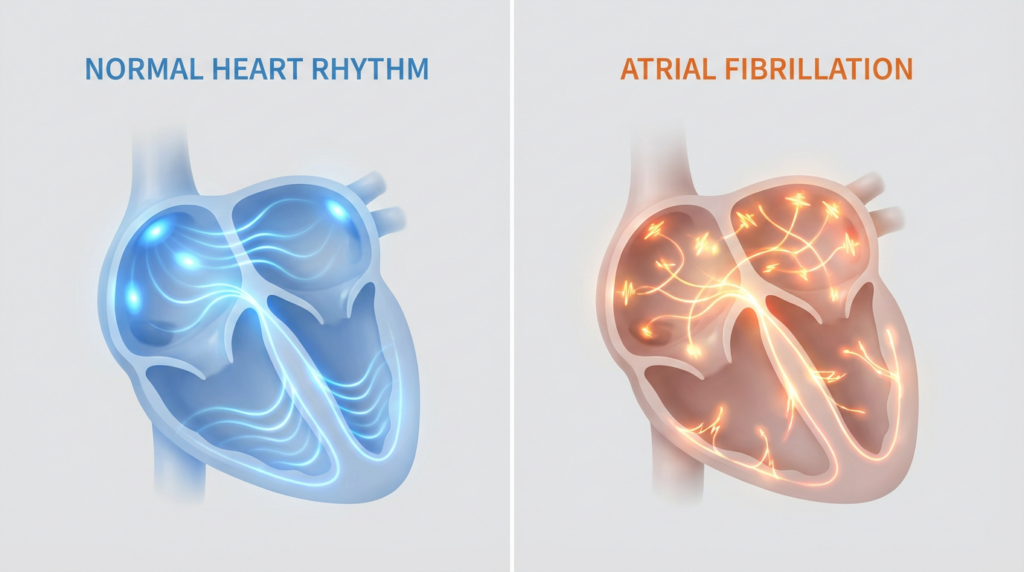

¿Qué es la fibrilación auricular?

La fibrilación auricular es una arritmia en la que la actividad eléctrica de las aurículas se vuelve caótica y desorganizada.

En lugar de un latido coordinado, el corazón recibe múltiples señales eléctricas desordenadas que provocan: